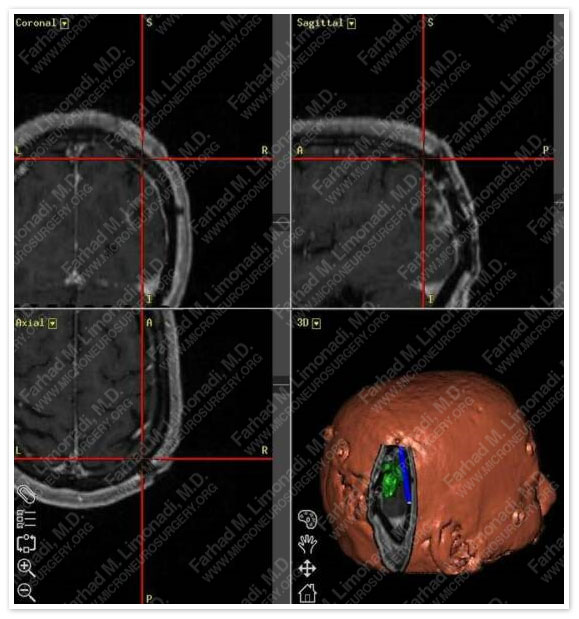

Computer Navigation

Computer navigation shows a virtual window through the skull over the tumor. The actual craniotomy size was as small as the tumor.